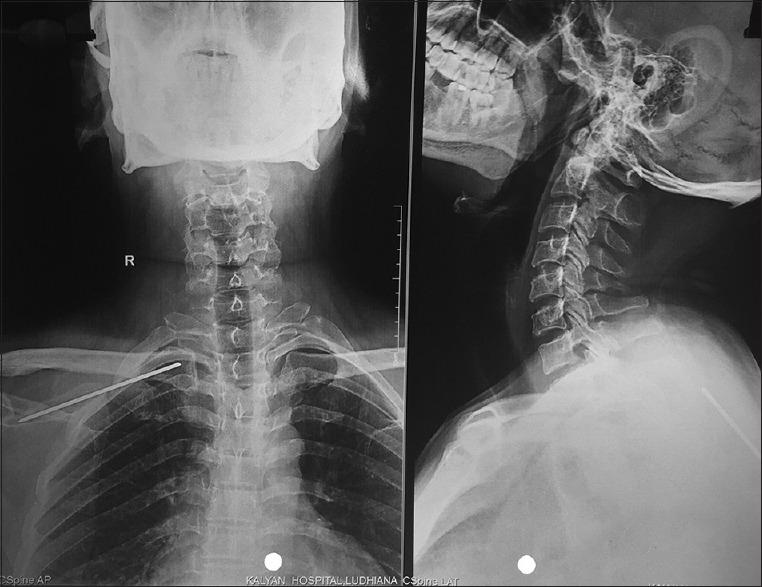

Kirschner wire in acromoclavicular joint - Should chest X-ray be recommended in preoperative evaluation of the patient?

https://cdn.ncbi.nlm.nih.gov/pmc/blobs/f594/6598584/b35b10e3a43d/JOACP-35-268-g001.jpg